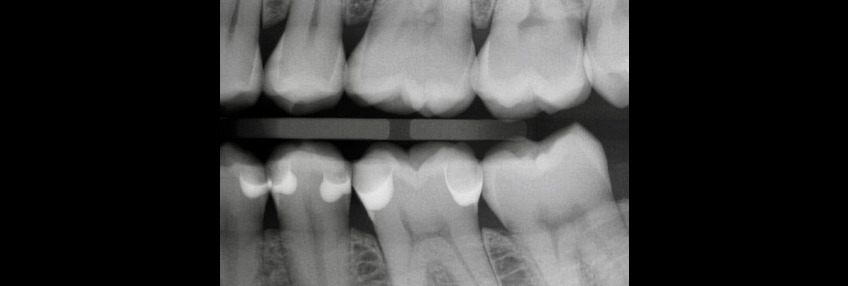

In the first two articles of this series, we first examined the common problems of closing the Class II box, and then looked at specific techniques for managing direct resin. At the end of that second article, I introduced the concept of the centripetal technique, whereby, after bonding, the proximal box is built, converting the Class II into a Class I restoration. The Class I portion is then restored on a cusp-by-cusp basis.

As I wrote in that article, “the proximal box is divided into two portions, or increments: a gingival portion from the gingival margin to the level of the occlusal isthmus and an occlusal portion from the gingival portion to the maximum height of the marginal ridge.”

In this final article in the series, we are going to walk through the main processes and strategies that make up the centripetal technique, starting with the gingival increment.